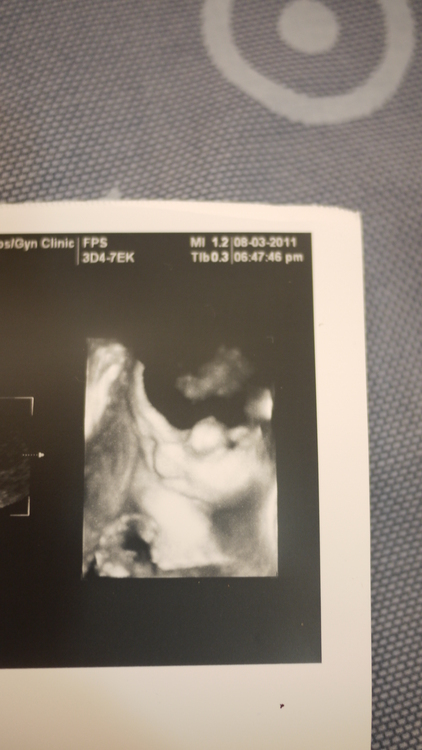

32周產檢還是問了一下醫師...好奇的想看一下...醫師看了一下寶寶位置...只拍到側臉

寶寶一直在睡覺...但還一邊吸著手手...真的好可愛!!...

這是側臉,拍的那天從頭到尾都在睡覺,有點失望+浪費錢說.......

好不容易捕捉到張開嘴打呵欠,趕快拍下!